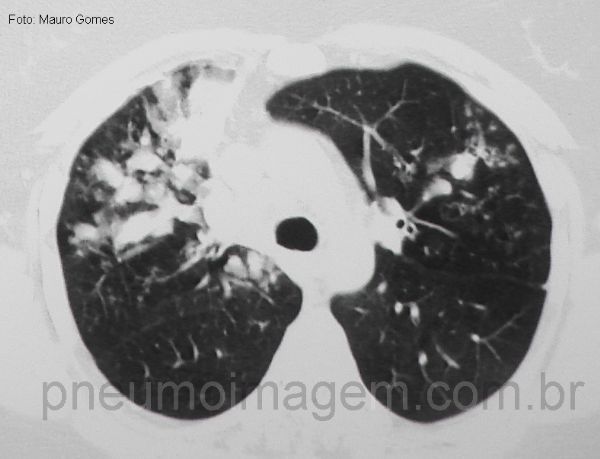

Na Aspergilose Broncopulmonar Alérgica (ABPA) as bronquiectasias são centrais (seta branca) e impactação de muco (seta vermelha), formando o sinal do dedo de luva. Ainda pode-se observar perfusão em mosaico (lobo inferior direito) e nódulos centrolobulares (círculo amarelo).

In Allergic Bronchopulmonary Aspergillosis (ABPA) bronchiectasis is central (white arrow) and mucus impaction (red arrow), forming the sign of the gloved finger. A mosaic perfusion (right lower lobe) and centrilobular nodules (yellow circle) can still be seen.